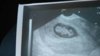

Jeszcze chyba za wcześnie zeby mu cos dyndalo [emoji39] wiec pewnie pepowinaŚliczne te nasze maluszki, a to mój, kurcze coś mu dynda między nogami, też to widzicie?

Choć mam nadzieje ze to pepowina, bo marzę o córeczce :-)

Zobacz załącznik 776457